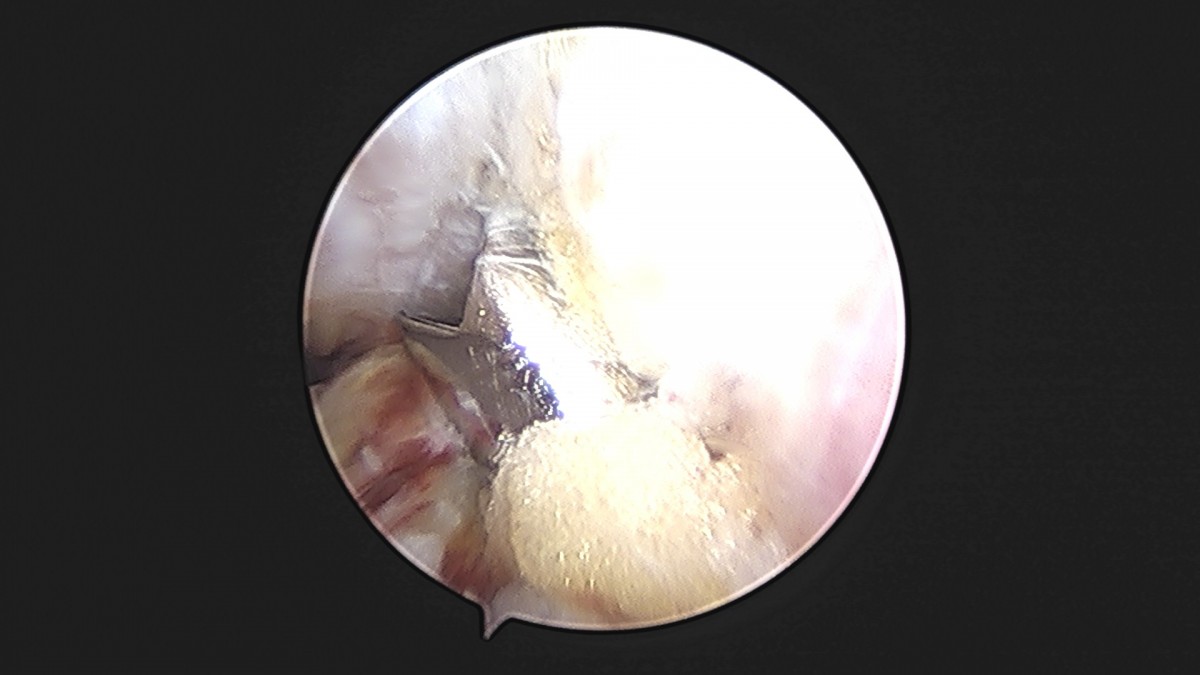

이재상원장님 발목 인대 봉합술 박찬O 환자

dae765e4d9ac96aee867c9d6292d8784_1758007285_0376.jpg